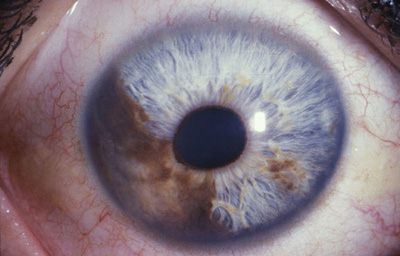

Melanoma difuso del iris

Archivo Fotográfico Dr. Francisco Barraquer.

Melanoma difuso del iris

Archivo Fotográfico Dr. Francisco Barraquer.

En la forma difusa, se aprecia una capa plana, irregular, de células pigmentadas o no, con un compromiso del iris confluente o multifocal; representa el 10% de todos los melanomas del iris. Su diagnóstico es difícil y demorado, porque frecuentemente los pacientes están siendo tratados por el cuadro de glaucoma secundario que generan. Clínicamente lo mas frecuente en su presentación es encontrar heterocromía hipercrómica unilateral y glaucoma secundario. Como dato importante, los melanomas difusos comparandolos a otros melanomas del iris, muy frecuentemente están compuestos por células epiteliodes, que tienen poca cohesión y se dispersan con facilidad en el humor acuoso, haciendo siembras en el trabéculo y estroma iridiano, y por esta razón son considerados de alto riesgo para metástasis. (33)